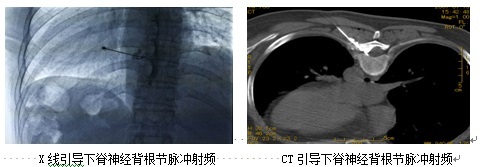

“如果神经阻滞有一定效果,但还没达到患者的预期目标,我们还能够针对神经进行脉冲射频调控治疗。”万丽说,治疗时,把射频针穿刺到病变神经周围,通过脉冲电刺激,对神经进行调控,减轻神经周围炎症,促进神经修复,从而缓解疼痛。